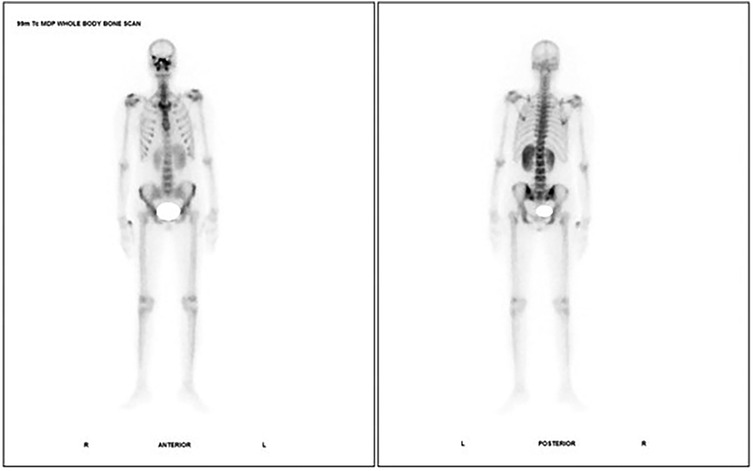

A Case series of 99mTc-MDP Bone Scintigraphy (Planar and SPECT CT) in Mucormycosis IN THE ERA OF COVID 19

Mucormycosis is a serious fungal infection affecting immunocompromised individuals, caused by fungi from the Mucorales order, particularly Rhizopus species. It primarily spreads through inhalation of spores, with diabetes, cancers, organ transplants, immunosuppressive drugs, and COVID-19 being major risk factors. The infection manifests in various forms such as encephalic, cutaneous, gastrointestinal, pulmonary, and rhino cerebral, often leading to tissue necrosis and blood vessel invasion. Imaging diagnosis is aided by CT and MRI scans, while 99m Tc MDP bone scintigraphy has found to be a more accurate imaging tool to look for bone remodelling and erosive changes associated with invasive fungal sinusitis including mucormycosis. Treatment involves prompt surgical debridement and addressing the underlying immune deficiency. Here we present a series of cases where 99m Tc MDP bone scintigraphy played a key role in management of mucormycosis of the head. In conclusion, 99mTc MDP scintigraphy is a promising tool for evaluation, guiding diagnosis and management of mucormycosis.